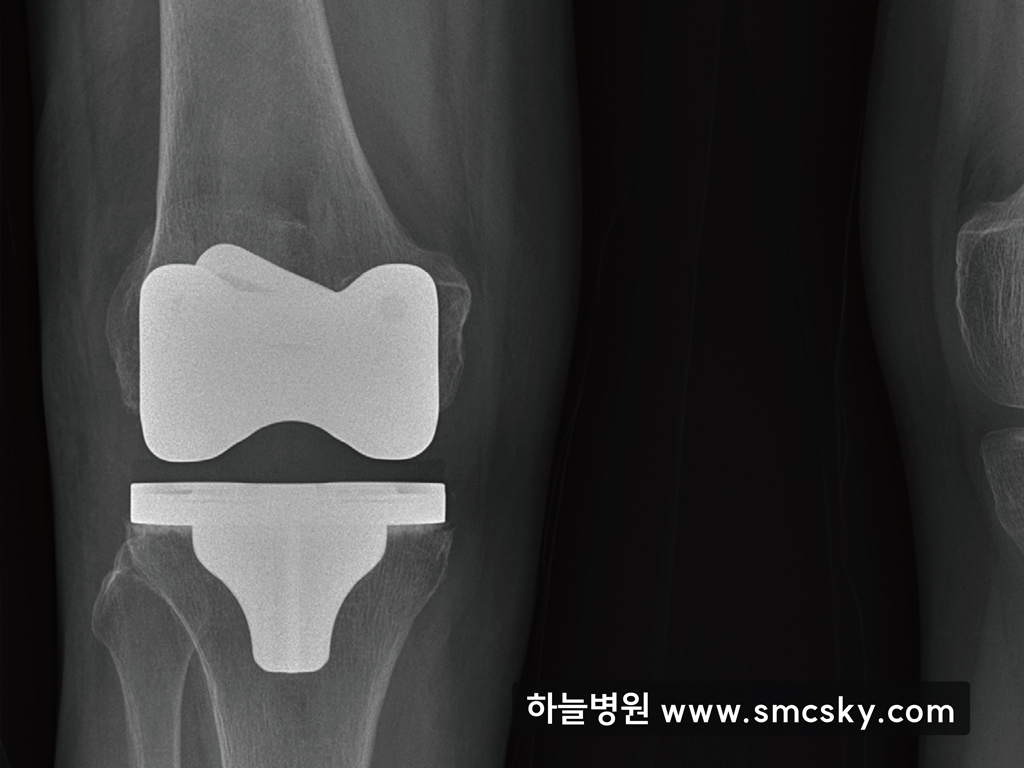

가장 심한 단계인 4기에 이르면 연골이 거의 닳아 없어지면서 극심한 통증과 함께 관절 변형이 고착화됩니다. 이 시기에는 손상된 관절 부위를 인공 구조물로 대체하는 인공관절 치환술이 유일한 해결책이 될 수 있습니다.